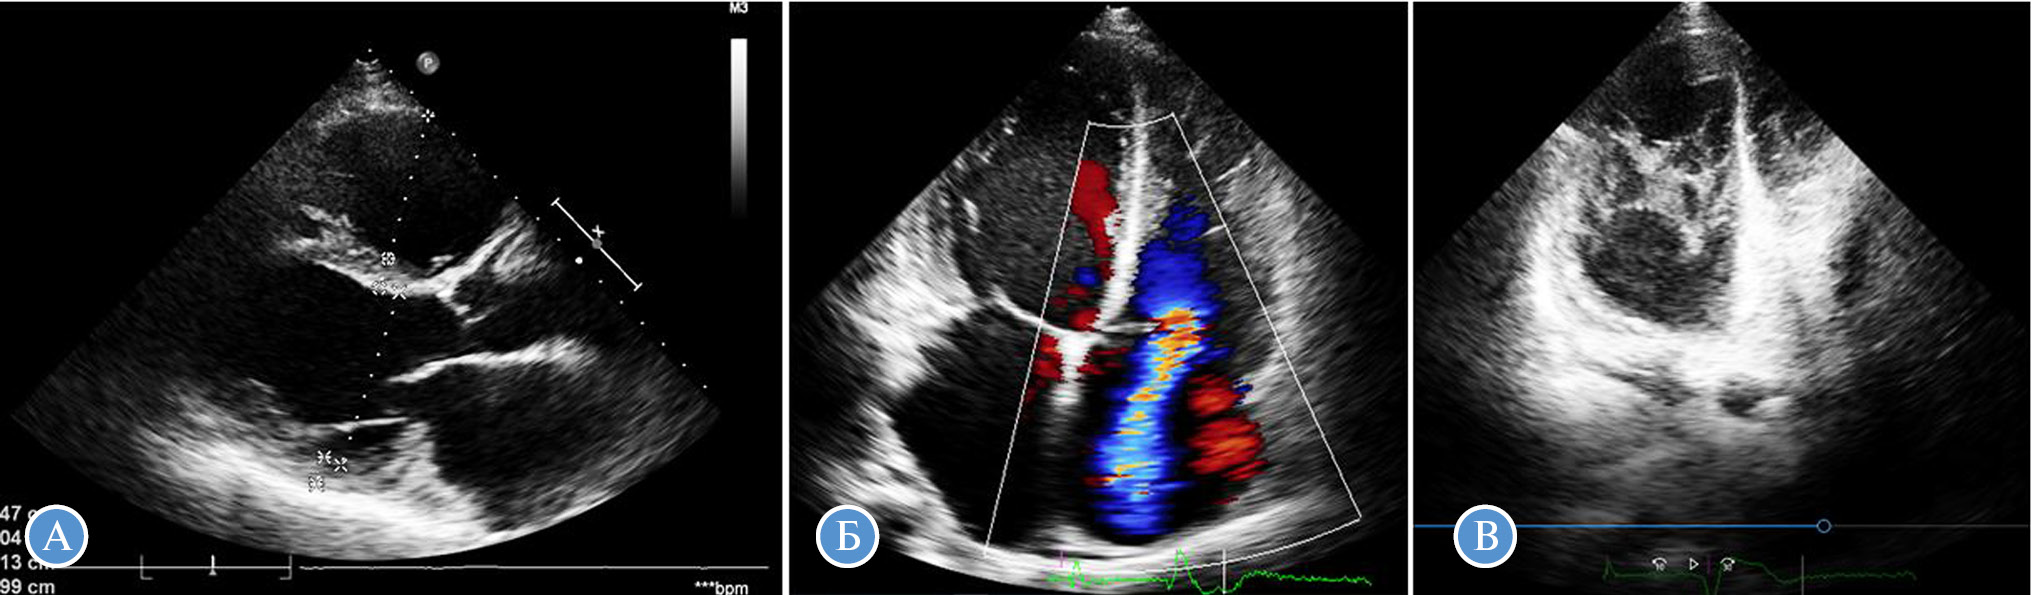

Рис. 3. ЭхоКГ пациента с сочетанием аритмогенной дисплазии правого желудочка и некомпактного миокарда левого желудочка (пробанд № 2).

А — дилатация левого желудочка и правого желудочка (конечный диастолический размер ЛЖ — 6,1 см, переднезадний размер правого желудочка — 5,0 см); Б — выраженная трикуспидальная регургитация; В — некомпактный слой в левом желудочке